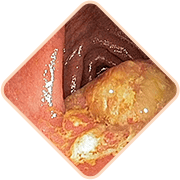

A tudósok új fejlesztése 2017-ben igazi áttörést jelentett az aranyér elleni küzdelemben. A tudósok gyakorló proktológusokkal közreműködésével létrehoztak egy egyedülálló és természetes gyógymódot, amely megszünteti az aranyér minden lehetséges problémáját és annak szövődményeit.

A Hemoren egy krém, amely:

• - már 2 alkalmazás után elállítja a vérzést;

• - már 3 alkalmazás után enyhíti a fájdalmat;

• - ne ad esélyt a betegség visszatérésére, ha kúraszerűen megismétli a használatot.

• Visszaadja a vénák tónusát és rugalmasságát a cickafarkfű-kivonatnak és a fűrészpálma-kivonatnak köszönhetően

• Indítsa be a végbélnyílás szöveteinek regenerációját a sabal pálma, a tölgykéreg, az aloe kivonatának segítségével

• Akadályozza meg vagy szüntesse meg a fertőzéseket és a gennyes folyamatokat a kamilla, a burgonya és a fokhagyma összetevőinek használatával

• Megakadályozza az aranyér visszatérését a celandinnak köszönhetően